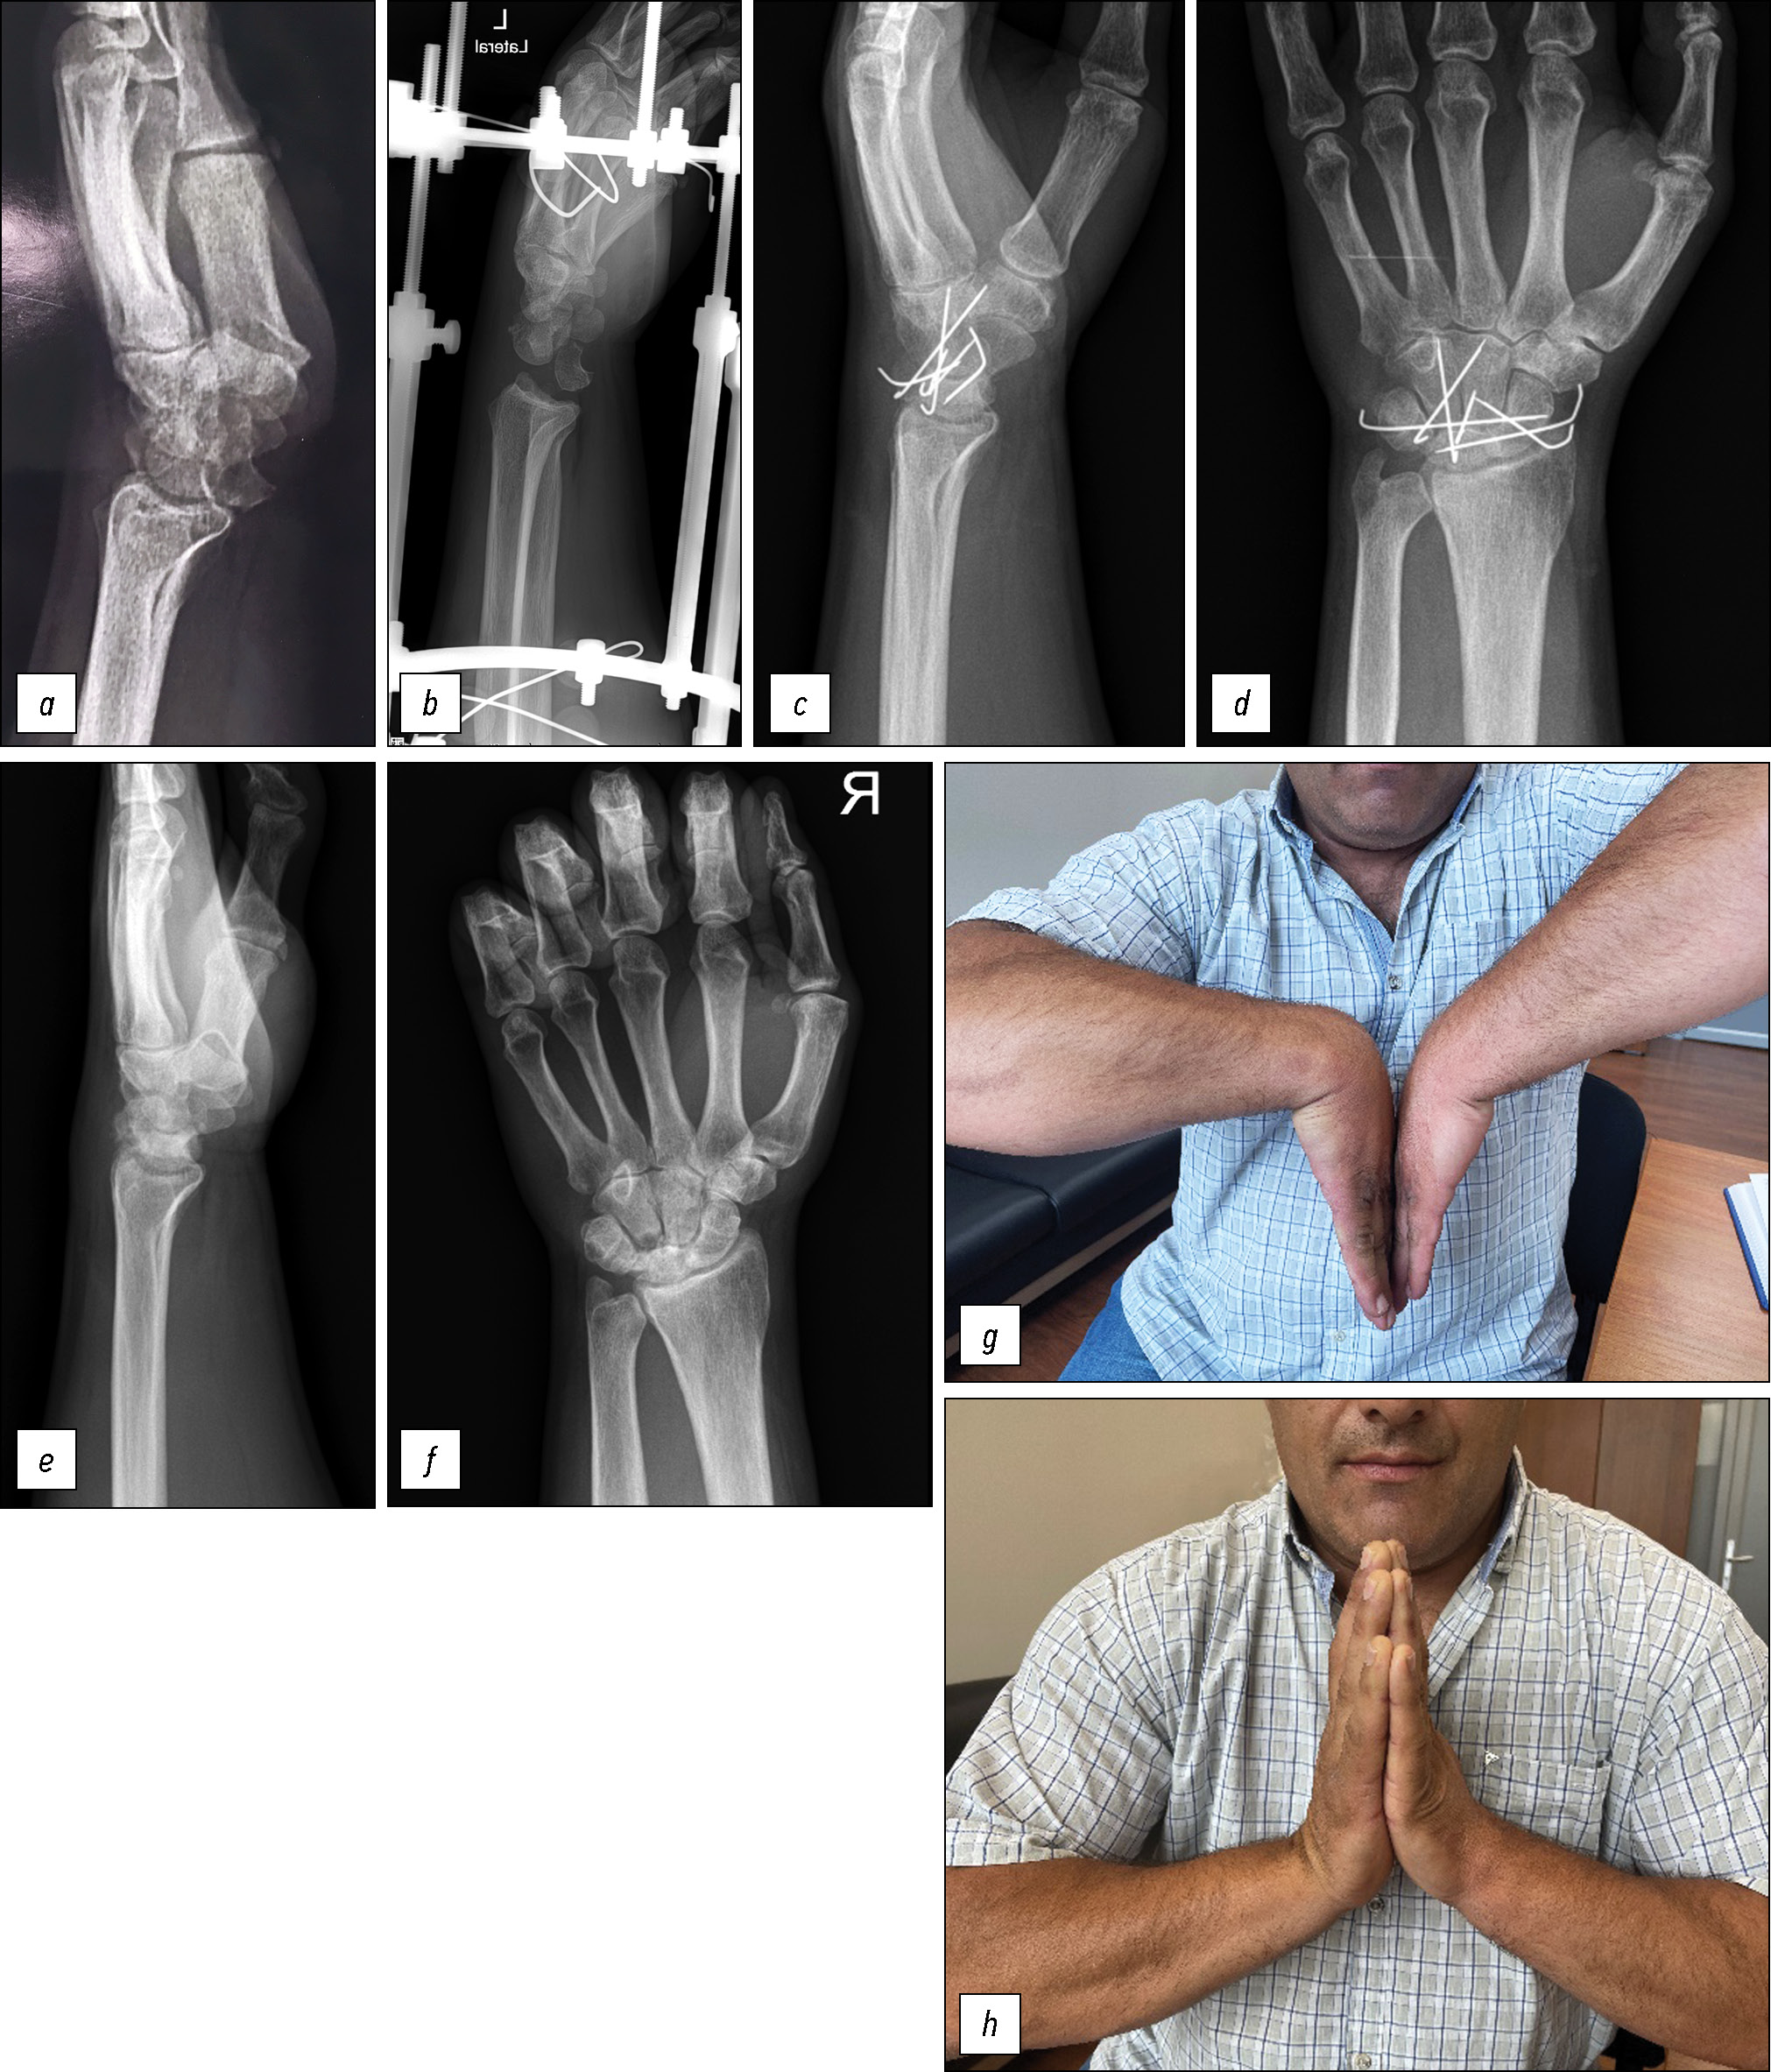

Пациент, 39 лет, обратился с жалобами на постоянную боль, ограничение движений в левом (пациент правша) кистевом суставе, нарушение чувствительности на кисти. 19 месяцев назад повредил кистевой сустав при падении на ладонь. Находился на лечении у хирурга по месту жительства. По поводу «ушиба тяжёлой степени» носил ортез и получил несколько курсов физиопроцедур и массажа. Боли и нарушения функции сохранялись. Только спустя 19 месяцев был диагностирован перилунарный вывих в кистевом суставе (рис. 2, а). При осмотре отмечен умеренный отёк в области кистевого сустава. Движения резко болезненные, ограниченные: сгибание 10 градусов, разгибание 10 градусов. Сила кулачного схвата — 11 кг, на здоровой стороне — 58 кг. Гипестезия в зоне срединного нерва на кисти (ладонная поверхность I, II, III пальцев). Учитывая давность травмы, лечение проводилось в два этапа. На первом этапе монтирован аппарат Илизарова для предварительного постепенного растяжения кистевого сустава. Аппарат монтирован из двух опор (кольца диаметром 140 мм). Темп дистракции составил 1 мм в сутки. Спустя 3 недели достигнут существенный зазор между костями запястья — на боковой рентгенограмме интервал между дистальным полюсом головчатой кости и суставной поверхностью лучевой кости был эквивалентным ширине полулунной кости, находящейся в положении вывиха (рис. 2, b). На втором этапе аппарат Илизарова демонтирован и выполнено открытое вправление вывиха. Операция выполнена через тыльный продольный доступ. После вскрытия полости сустава удалены рубцы, покрывающие суставные поверхности головчатой, полулунной и лучевой кости. Полулунная кость репонирована и фиксирована спицами 1 мм в диаметре. Благодаря предварительной дистракции и достаточной мобильности костей запястья процесс удаления рубцов и репозиции не был травматичным. В послеоперационном периоде осуществлялась иммобилизация с помощью гипсовой шины, которая через две недели (после снятия швов) была заменена на циркулярную гипсовую повязку. Через 3 месяца после операции повязка снята, пациенту рекомендованы съёмный ортез и гимнастика. Через 4 месяца после открытого вправления болей в покое нет, чувствительность в пальцах восстановилась. Пациент вернулся к офисной работе. На рентгенограммах через 6 месяцев после операции соотношения в суставе правильные (рис. 2, c, d). Спицы удалены. На рентгенограммах через 18 месяцев после второго этапа лечения признаки деформирующего остеоартрита (ДОА) кистевого сустава, резорбции проксимальной части крючковидной кости (рис. 2, e, f) без значительных клинических проявлений. В покое и повседневной деятельности боли не возникают. Незначительные боли испытывает после тяжёлой продолжительной физической нагрузки. Сила кулачного схвата — 37 кг, амплитуда движений в кистевом суставе (сгибание / разгибание) — 95 градусов (рис. 2, g, h). Оценка функционального результата по системе Mayo — 70 баллов, показатели QuickDASH — 25, VAS — 2 (после тяжёлой продолжительной физической нагрузки).

Рис. 2. Рентгенограммы кистевого сустава пациента 8: а — рентгенограмма в боковой проекции до начала лечения, b — рентгенограмма в боковой проекции в процессе дистракции, c, d — рентгенограммы в боковой и прямой проекции через 6 месяцев после второго этапа операции, e, f — рентгенограммы в боковой и прямой проекции через 18 месяцев после второго этапа операции, g, h — фото кистевых суставов в положении сгибания и разгибания.

Fig. 2. Radiographs of the wrist joint in patient 8: a, lateral radiograph prior to treatment; b, lateral radiograph during distraction; c, d, lateral and anteroposterior radiographs 6 months after the second stage of surgery; e, f, lateral and anteroposterior radiographs 18 months after the second stage of surgery; g, h, photographs of the wrist joints in flexion and extension positions.